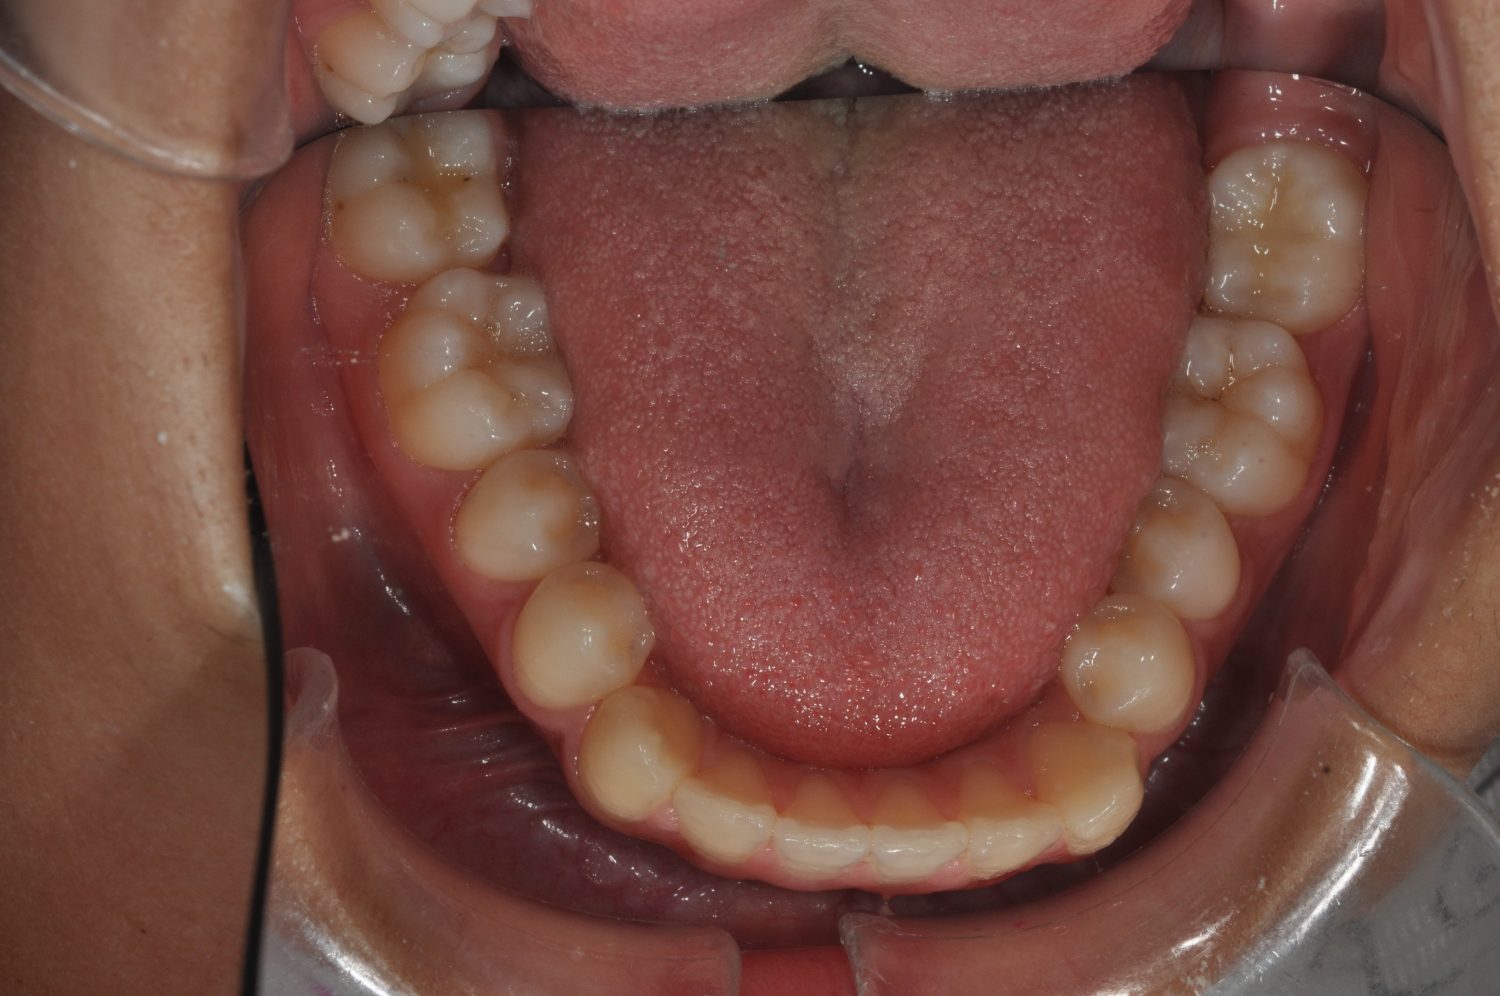

| 主訴 | 前歯の出っ歯を直したい |

| 治療内容 | 上下顎とも標準範囲であるが、上下顎前歯ともに唇側傾斜による、上下顎前突。上顎小臼歯を抜去し配列を行うこととした。 |

| 治療期間 | 2年1ヶ月 |

| 想定されたリスク | 矯正器具の装着に伴い、むし歯や歯周病のリスクがありました。また、歯根吸収や歯肉退縮のリスクもありました。 |

上下顎前歯の唇側傾斜による上下顎前突。オーバージェットが大きいため、上顎のみの抜歯で配列を行った。